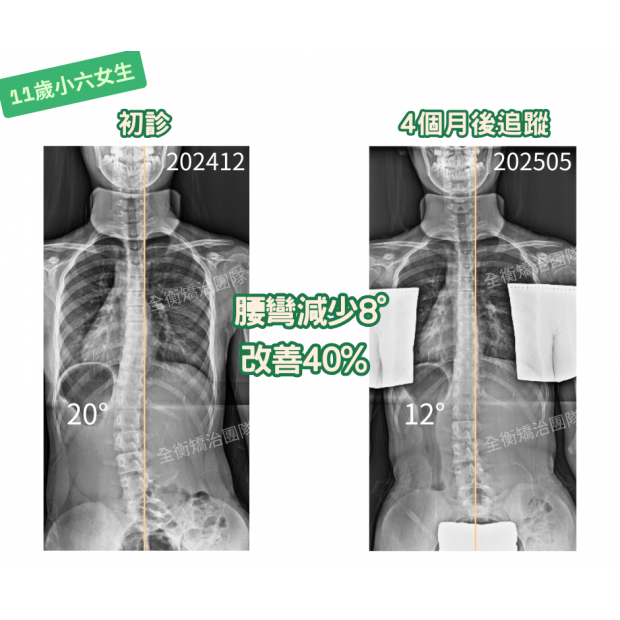

11歲20度女生 矯治4個月進步 40_.png

11歲小六女生,4個月改善40%!黃金矯治期真的不能等!

11歲女生,腰彎20度,正值青春快速成長期惡化風險高,

矯治4個月後追蹤,側彎度數從20°→12°,大幅改善40%!